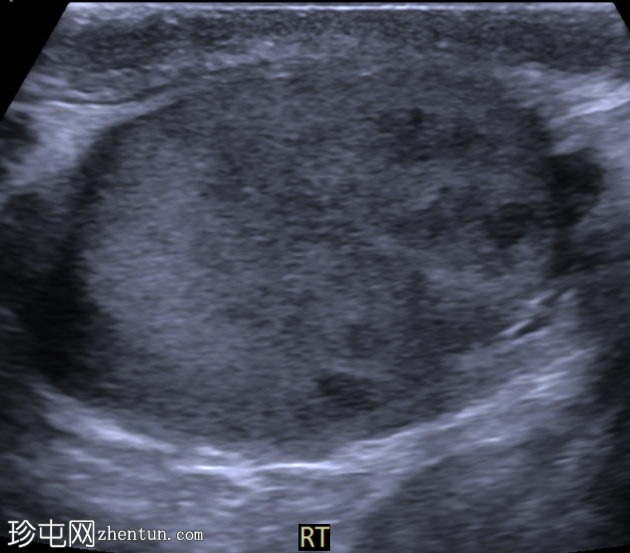

右侧睾丸内可见一大小约3.0 x 5.0 cm的异质性分叶状低回声肿块。肿块内未见囊性区域或钙化。彩色多普勒超声检查显示肿块内血流丰富。左侧睾丸正常。